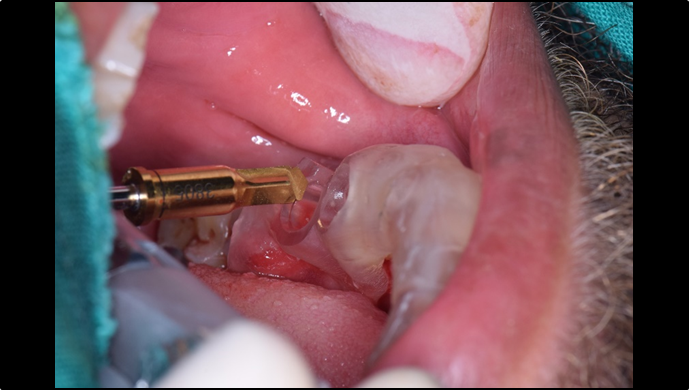

Clinical case: Extraction, immediate placement & loading using

R2GATE solution in aesthetic zone

- Courtesy of Dr. Jong-Cheol Kim, Korea-

Dr. Jong Cheol Kim, immediate loading, digital guided surgery, Digital ONE-DAY Implant, maxillary anterior, #21, guided surgery, immediate loading, AnyRidge, R2GATE, Mega ISQ, MEG Torq, R2GATE Full Surgical Kit

AnyRidge implant system, R2 Guide, R2GATE Full Surgical Kit, Mega ISQ